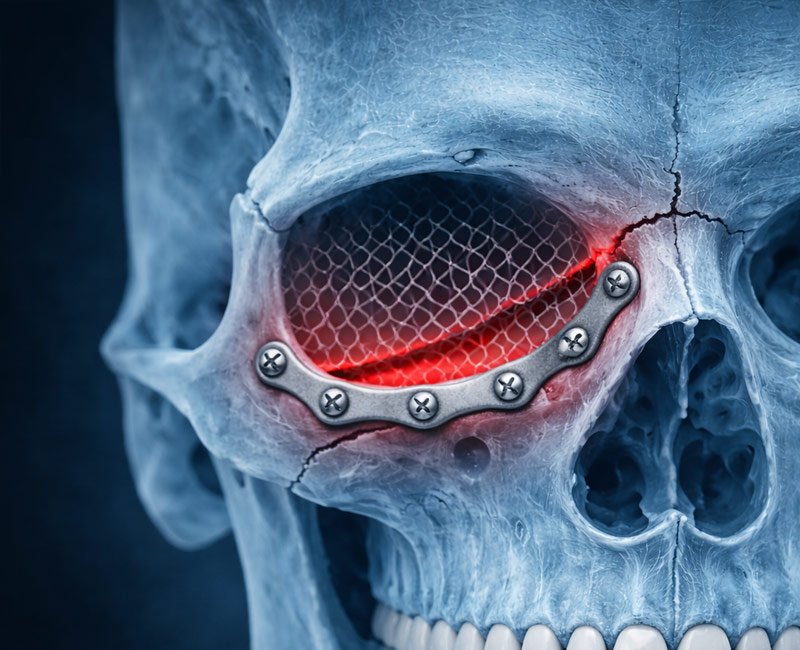

Fracturas faciales - Cirugía Maxilofacial

Las fracturas faciales son lesiones que pueden afectar los huesos del rostro después de accidentes, caídas o traumatismos, comprometiendo la función, la respiración y la armonía facial. La cirugía maxilofacial permite diagnosticar y tratar estas lesiones con precisión, buscando recuperar la estabilidad ósea y una correcta cicatrización.

Tipos de fracturas faciales más frecuentes:

- Fractura de órbita

Fractura de órbita

Fractura de órbita